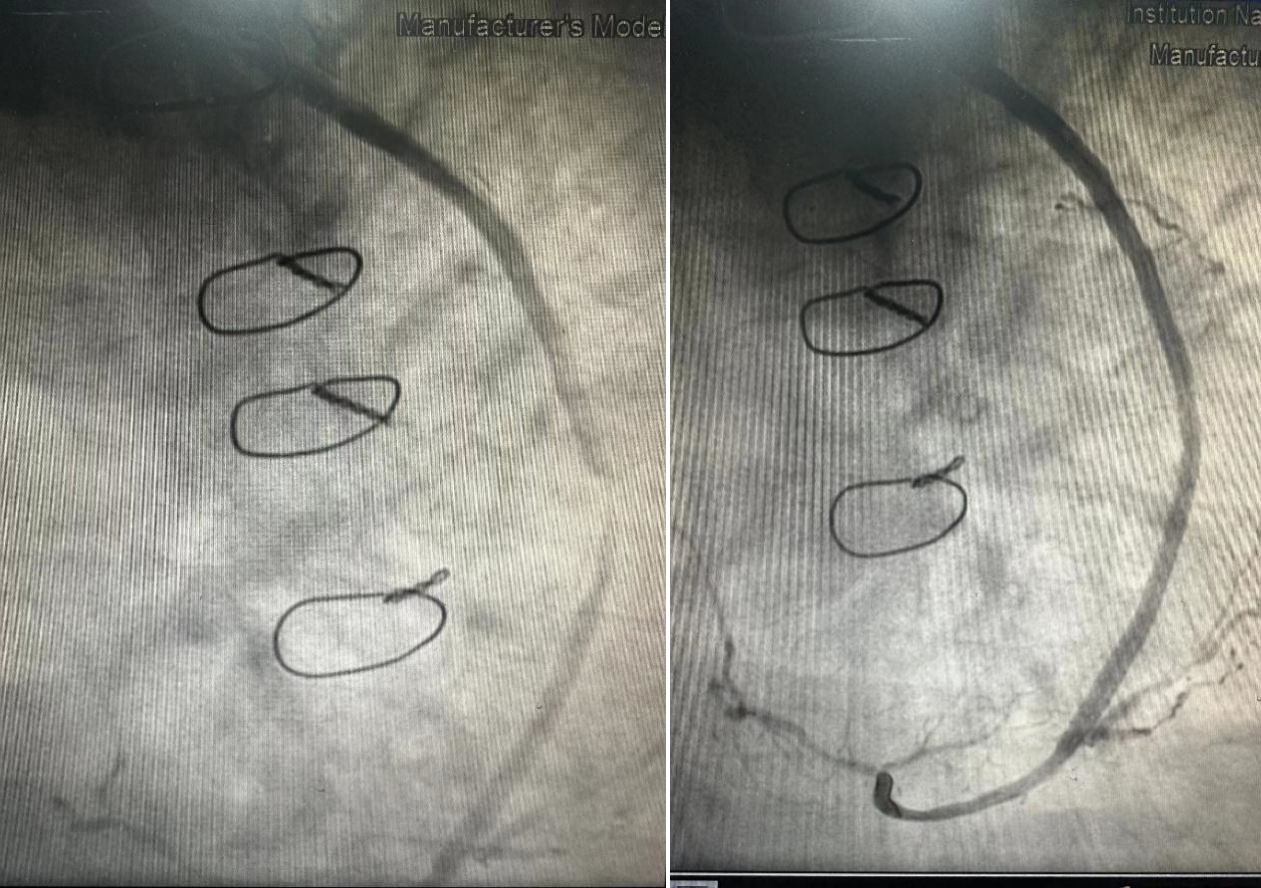

术中,医疗团队发现患者钝缘支吻合口前桥血管狭窄约90%。在征求家属意见后,医疗团队决定对升主动脉-钝缘支桥血管做介入治疗。大家快速准确地对病变血管的范围进行判断,并选择合适的球囊和支架进行干预治疗。手术存在诸多可能一触即发的危险因素,任何一点差池和意外,都可能会引起无法挽回的后果。杨滨主任医疗团队凭借着高超的技术、丰富的经验、坚强的毅力和密切的团队协作精神,精准、安全、高效地为患者成功实施了介入治疗手术。